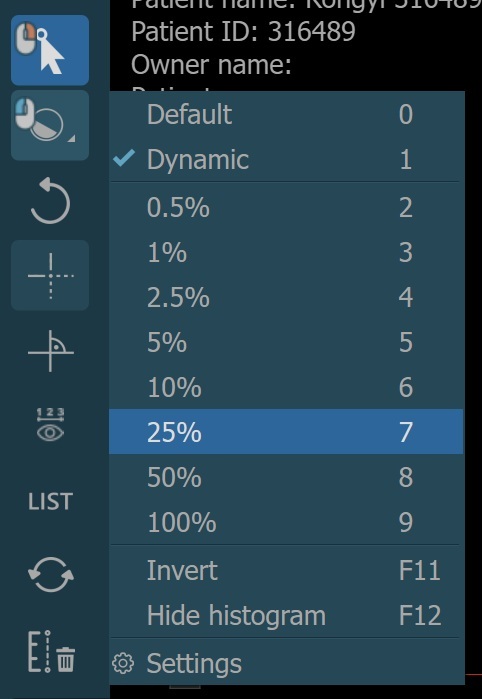

The preset values for the dynamic windowing mode are represented as a percentage of the maximum determined windowing range. All of the preset values are available in the windowing menu when dynamic mode is active.

Alternatively, the percentage value of the maximum determined windowing range can be adjusted by using the Dynamic slider or the subsequent input field available in the windowing section when the dynamic mode is active.